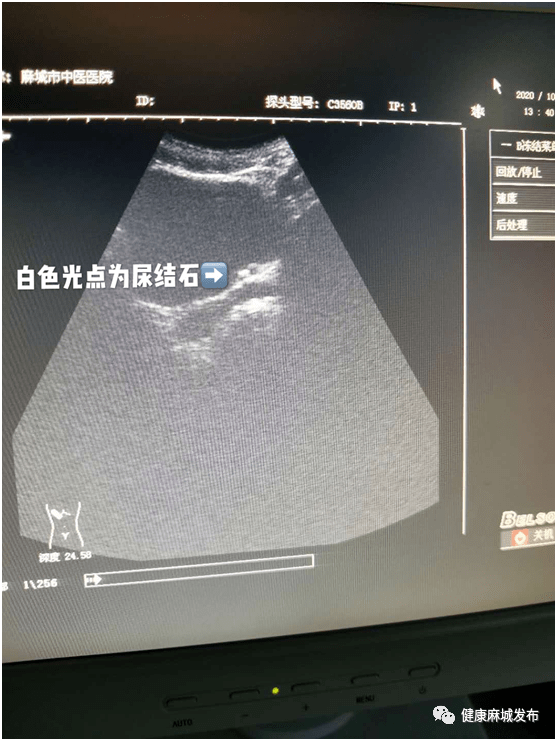

石石牵挂碎碎平安麻城市中医医院开展多例体外冲击波碎石术

图片尺寸557x741